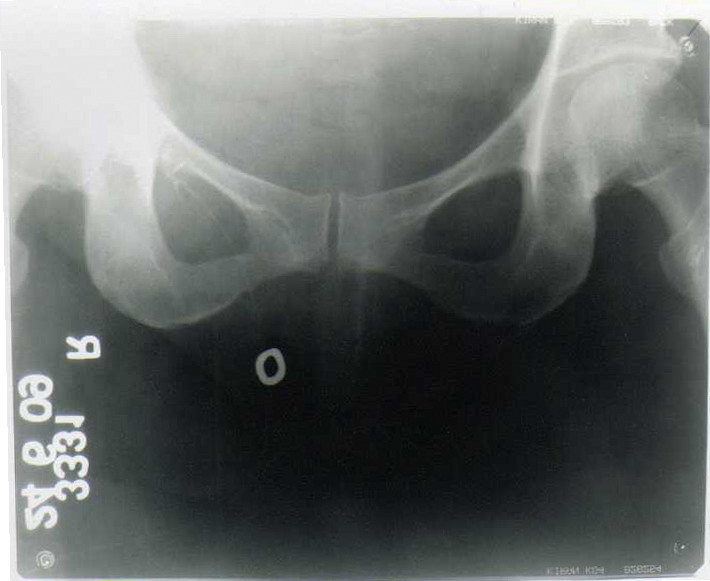

Fig 2: Sinogram showing collection of the dye at the level of Right pubic ramus.